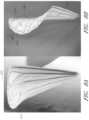

FIG.13C illustrates a perspective view of an embodiment of the coaptation element.

FIGS.13D-E illustrate side views of an embodiment of the coaptation element.

FIGS.13F,13G, and13H illustrate the geometry of an embodiment of the coaptation element juxtaposed on a cone.

In some embodiments, as shown inFIG.13F, the geometry of thecoaptation element500 conforms substantially to a portion of the surface of a cone. Embodiments describe alength600 within a range of about 20 to about 80 mm along the primary axis of rotation between the apex602 and thebase arc606, and aradius604 of the base arc within the range of from about 25 to about 35 mm. Also, the linear distance between the two ends of the base arc has a length within the range of from about 20 to about 60 mm. The two endpoints of the base arc lie on the surface of the cone.

In other embodiments, as shown inFIGS.13G and13H, the implant conforms substantially to a portion of the surface of a cone for about 50 to about 70% of thetotal height608 measured along thelongitudinal axis614 of the cone, then the implant flares radially outwardly from the cone. That radiallyoutward flare612 can be considered to have a radius within a range of from about 5 to about 12 mm. Theinflection point610 where the flare departs from the wall of the cylinder can be located within a range of distance from about 10 to about 70 mm along the longitudinal axis. The inflection point may be at about 45 to about 75% of the total length along the longitudinal axis. The implant can also have a total length along the axis within the range of from about 25 to about 100 mm, and the base arc can have a radius (measured perpendicular to the axis) within the range of from about 35 to about 45 mm.